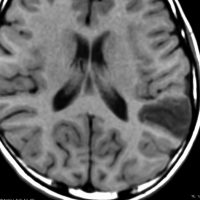

3歳で最初のてんかんらしいと言われる発作があり,その後は発作は見えず自動症と診断され徐々に学習能力の低下が認められ,7歳の時に外来を訪れました。週に3回くらい腹痛や嘔気があってすぐに眠くなってしまう。耳鳴がすごくてしばらく何も聞こえなくなってしまう,話も理解できなくなるなど,側頭葉てんかんの特徴をたくさんエピソードとして持っていましたが,症候性てんかんとは診断されませでした。側頭葉にどのような機能があるのかを証明してくれる症例でもあります。

典型的なDNTの画像で説明するまでもありません。ガドリニウムでは全く増強されませんでした。左上側頭回と角回の境界域に存在します。

側脳室壁のあたりまで全摘出しました。とても柔らかい腫瘍で吸引できました。

病理は,粘液気質を背景に小型円形の核を有する細胞が増殖し,肺胞用構造を呈していました。その中にやや大型の神経細胞が多数混在するものです。

術前発作期間が長いと症状の回復が不良であるという残念な例でもありました。